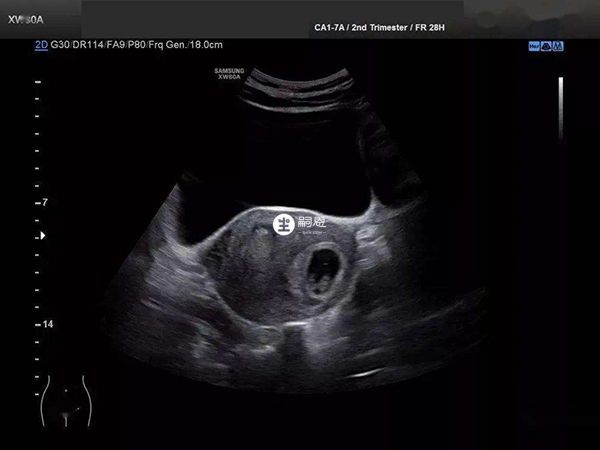

28歲,結婚3年多了,最近開始備孕,這個月沒有來月經,猜測自己大概中了,就去買了驗孕棒測,發現確實已經懷上了,然後昨天去醫院做了陰超檢查,醫生說我是疑似宮角妊娠,可能會考慮清宮,否則對自身傷害後很大,但具體需要孕周大一些才能確認,請問我這樣太早去做孕檢,會出現誤診宮角妊娠的情況嗎?太早孕檢做陰超確實有可能會出現宮角妊娠誤診的情況,一般建議在確定懷孕後的5-8周左右再去醫院做陰超檢查,這樣出現誤診宮角妊娠的概率就會小很多。雖然目前醫院的b超裝置都是較為完善的,且手段很高,但如果懷孕較早就去做陰超,這時胚胎還未完全固定位置,陰超就很可能會提示是近宮角妊娠,出現這種情況就需要隨訪,每週觀察胚胎挪動情況。

宮角妊娠是異位妊娠的一種,非常罕見,是指胚胎種植在子宮角部。臨床上宮角妊娠診斷的標準不能僅看一次的陰超結果,需要結合多次的陰超/b超結果才行。宮角妊娠正常情況下在6周左右就可以確診,如果6周時孕囊著床在宮角的部位,那麼就需要及時終止妊娠,因為12周後胚胎組織在宮角逐漸增大,撐破宮角處肌層時會造成宮角破裂,從而容易出現出血洶湧,導致失血性休克。